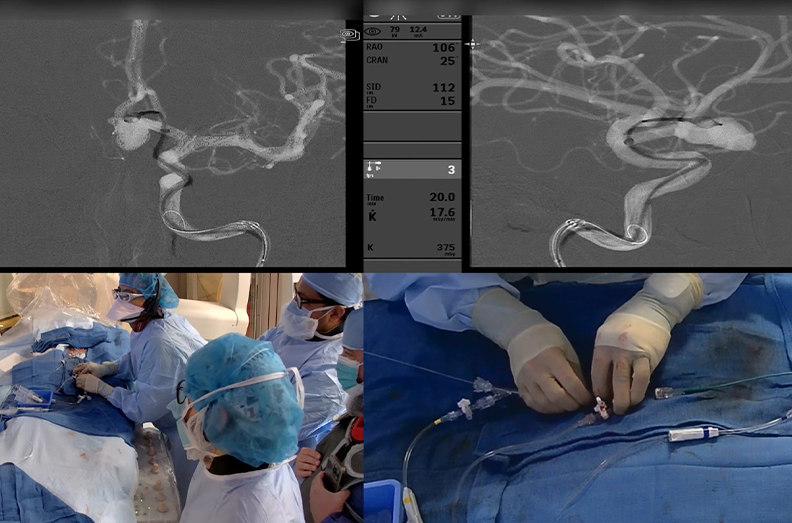

Dr. Mehta, a vascular and interventional neurologist and medical director of the Comprehensive Stroke and Neurointerventional Surgery programs at the Memorial Neuroscience Institute, performed the first live-streamed endovascular neurosurgery to fully secure a complex brain aneurysm using the novel Microvention Woven EndoBridge (WEB) device. Dr. Delgado, a neurointerventional radiologist at Abbott Northwestern Hospital in Minneapolis, logged on through the Proximie virtual operating room to provide technical guidance.

Drs. Mehta and Delgado utilized a minimally-invasive, endovascular treatment on Stephane Desjardins to treat the brain aneurysm, one that had a high probability of being fatal if it had ruptured and bled in the brain. The catheter-based image navigation procedure enabled the placement of the WEB device to secure the aneurysm. The procedure was a success due to the real-time virtual proctoring made possible with the Proximie system.